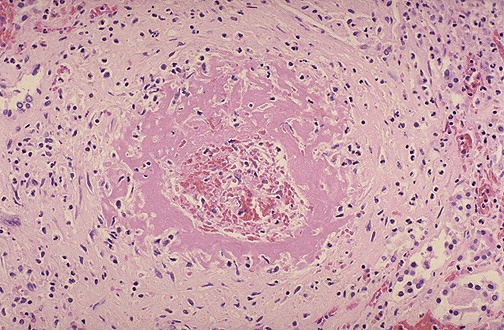

There are changes in the medium to small arteries consisting of intimal proliferation as well as very prominent fibrinoid necrosis.